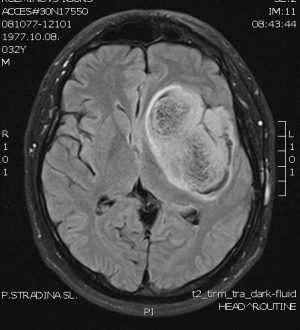

Π Π΅ΡΠ΅Π½ΠΈΠ΅ ΠΎ ΠΏΡΠΎΠ²Π΅Π΄Π΅Π½ΠΈΠΈ ΠΎΠΏΠ΅ΡΠ°ΡΠΈΠΈ ΠΈΠ»ΠΈ ΠΎ Π²ΡΠ±ΠΎΡΠ΅ Π΄ΡΡΠ³ΠΎΠ³ΠΎ Π²ΠΈΠ΄Π° Π»Π΅ΡΠ΅Π½ΠΈΡ (Ρ ΠΈΠΌΠΈΠΎΡΠ΅ΡΠ°ΠΏΠΈΡ, Π»ΡΡΠ΅Π²Π°Ρ ΡΠ΅ΡΠ°ΠΏΠΈΡ ΠΈ Ρ.Π΄.) Π±ΡΠ΄Π΅Ρ ΠΏΡΠΈΠ½ΡΡΠΎ ΠΏΠΎΡΠ»Π΅ ΡΡΠ°ΡΠ΅Π»ΡΠ½ΠΎΠ³ΠΎ Π΄ΠΈΠ°Π³Π½ΠΎΡΡΠΈΡΠΎΠ²Π°Π½ΠΈΡ Π²Π°ΡΠ΅Π³ΠΎ ΡΠΎΡΡΠΎΡΠ½ΠΈΡ Π·Π΄ΠΎΡΠΎΠ²ΡΡ, Π° ΡΠ°ΠΊΠΆΠ΅ ΠΏΡΠΎΠ²Π΅ΡΠΊΠΈ Ρ Π°ΡΠ°ΠΊΡΠ΅ΡΠΈΡΡΠΈΠΊ ΠΎΠΏΡΡ ΠΎΠ»ΠΈ. ΠΡΠ΅ΠΆΠ΄Π΅ Π²ΡΠ΅Π³ΠΎ Π²Ρ ΠΏΡΠΎΠΉΠ΄Π΅ΡΠ΅ Π²ΠΈΠ·ΡΠ°Π»ΠΈΠ·Π°ΡΠΈΠΎΠ½Π½ΠΎΠ΅ ΠΈΡΡΠ»Π΅Π΄ΠΎΠ²Π°Π½ΠΈΠ΅ β Π² Π±ΠΎΠ»ΡΡΠΈΠ½ΡΡΠ²Π΅ ΡΠ»ΡΡΠ°Π΅Π² ΠΠ’ Π³ΠΎΠ»ΠΎΠ²Ρ ΠΈΠ»ΠΈ ΠΠ Π’ β ΠΊΠΎΡΠΎΡΠΎΠ΅ Π±ΡΠ΄Π΅Ρ ΠΏΡΠΎΠ²Π΅Π΄Π΅Π½ΠΎ Π² ΡΡΠΎΠ²Π΅ΡΡΠ΅Π½ΡΡΠ²ΠΎΠ²Π°Π½Π½ΠΎΠΌ ΠΈΠ½ΡΡΠΈΡΡΡΠ΅ Π²ΠΈΠ·ΡΠ°Π»ΠΈΠ·Π°ΡΠΈΠΎΠ½Π½ΠΎΠΉ Π΄ΠΈΠ°Π³Π½ΠΎΡΡΠΈΠΊΠΈ ΠΏΡΠΈ Π±ΠΎΠ»ΡΠ½ΠΈΡΠ΅ Β«ΠΠ΅ΡΡΠ»ΠΈΡ ΠΠ΅Π΄ΠΈΠΊΠ°Π» Π¦Π΅Π½ΡΡΒ». ΠΠ°ΡΠ΅ΠΌ Π±ΡΠ΄Π΅Ρ ΡΠ΅ΡΠ΅Π½ΠΎ, Π½Π΅ΠΎΠ±Ρ ΠΎΠ΄ΠΈΠΌΠΎ Π»ΠΈ ΠΏΡΠΎΠ²Π΅Π΄Π΅Π½ΠΈΠ΅ Π±ΠΈΠΎΠΏΡΠΈΠΈ β ΠΏΠΎΠ»ΡΠΈΠ½Π²Π°Π·ΠΈΠ²Π½ΠΎΠΉ ΠΏΡΠΎΡΠ΅Π΄ΡΡΡ, Π² Ρ ΠΎΠ΄Π΅ ΠΊΠΎΡΠΎΡΠΎΠΉ Π±Π΅ΡΠ΅ΡΡΡ ΠΌΠ°Π»Π΅Π½ΡΠΊΠΈΠΉ ΠΎΠ±ΡΠ°Π·Π΅Ρ ΡΠΊΠ°Π½ΠΈ ΠΈΠ· ΠΎΠΏΡΡ ΠΎΠ»ΠΈ. ΠΡΠΎΡ ΠΎΠ±ΡΠ°Π·Π΅Ρ Π±ΡΠ΄Π΅Ρ ΠΏΠΎΡΠ»Π°Π½ Π½Π° Π°Π½Π°Π»ΠΈΠ· Π² Π³ΠΈΡΡΠΎΠΏΠ°ΡΠΎΠ»ΠΎΠ³ΠΈΡΠ΅ΡΠΊΡΡ Π»Π°Π±ΠΎΡΠ°ΡΠΎΡΠΈΡ ΠΏΡΠΈ Π±ΠΎΠ»ΡΠ½ΠΈΡΠ΅, ΠΈ Π² Π»Π°Π±ΠΎΡΠ°ΡΠΎΡΠΈΠΈ ΡΠΌΠΎΠ³ΡΡ ΠΎΠΏΡΠ΅Π΄Π΅Π»ΠΈΡΡ, ΡΠ²Π»ΡΠ΅ΡΡΡ Π»ΠΈ ΠΎΠΏΡΡ ΠΎΠ»Ρ Π΄ΠΎΠ±ΡΠΎΠΊΠ°ΡΠ΅ΡΡΠ²Π΅Π½Π½ΠΎΠΉ ΠΈΠ»ΠΈ Π·Π»ΠΎΠΊΠ°ΡΠ΅ΡΡΠ²Π΅Π½Π½ΠΎΠΉ, Π° ΡΠ°ΠΊΠΆΠ΅ ΡΡΠ΅ΠΏΠ΅Π½Ρ Π΅Π΅ Π·Π»ΠΎΠΊΠ°ΡΠ΅ΡΡΠ²Π΅Π½Π½ΠΎΡΡΠΈ, Π΅ΡΠ»ΠΈ ΠΎΠΏΡΡ ΠΎΠ»Ρ Π·Π»ΠΎΠΊΠ°ΡΠ΅ΡΡΠ²Π΅Π½Π½Π°Ρ.

ΠΎΠΏΡΡ ΠΎΠ»Ρ Π³ΠΎΠ»ΠΎΠ²Π½ΠΎΠ³ΠΎ ΠΌΠΎΠ·Π³Π°